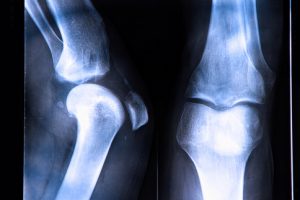

You Are Damaging Your Bones Everyday by Doing THIS